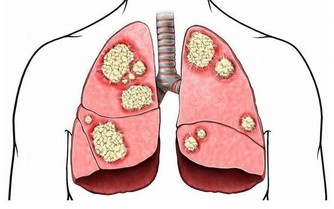

專家說,便秘患者因排便困難,通常會用力過大,引起腹壓升高,血壓也隨之升高;同時心率加快,導致心肌的耗氧量增加,心肌因而發生嚴重而持久的急性缺血,甚至發展為心肌梗死。

對心髒病人來說,便秘是引發急性心梗的危險因素之一。患者在用力排便時,血管壓力增加、血流速度加快,容易將附著在血管壁上的斑塊衝進血流,堵塞血管,引發急性心梗,甚至猝死。